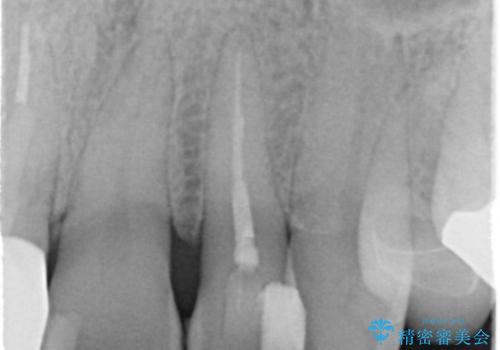

- 継ぎ接ぎになった前歯を綺麗にしたいとのことで来院されました。

継ぎ目のないクラウンで修復処置していきます。

- 左上2 仮歯+ジルコニアクラウン:11,000円+121,000円費用は治療当時の料金となります